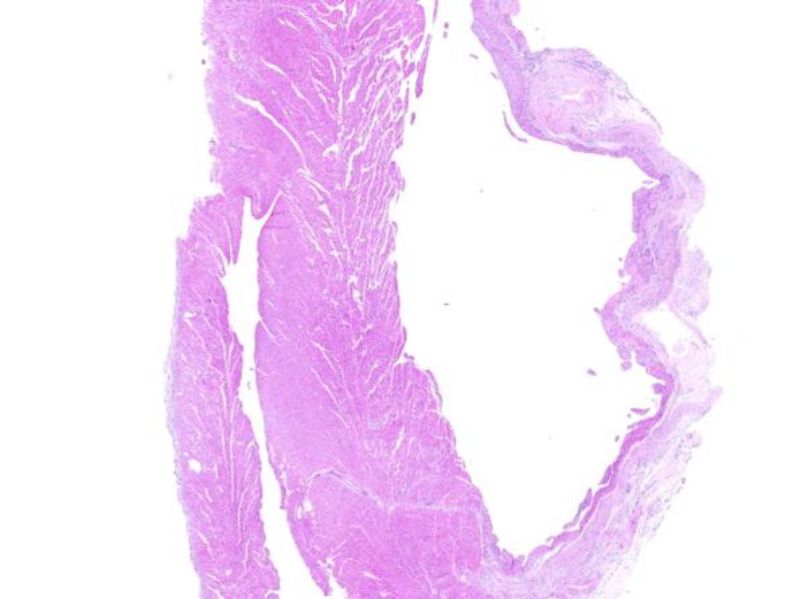

动脉粥样硬化动物模型